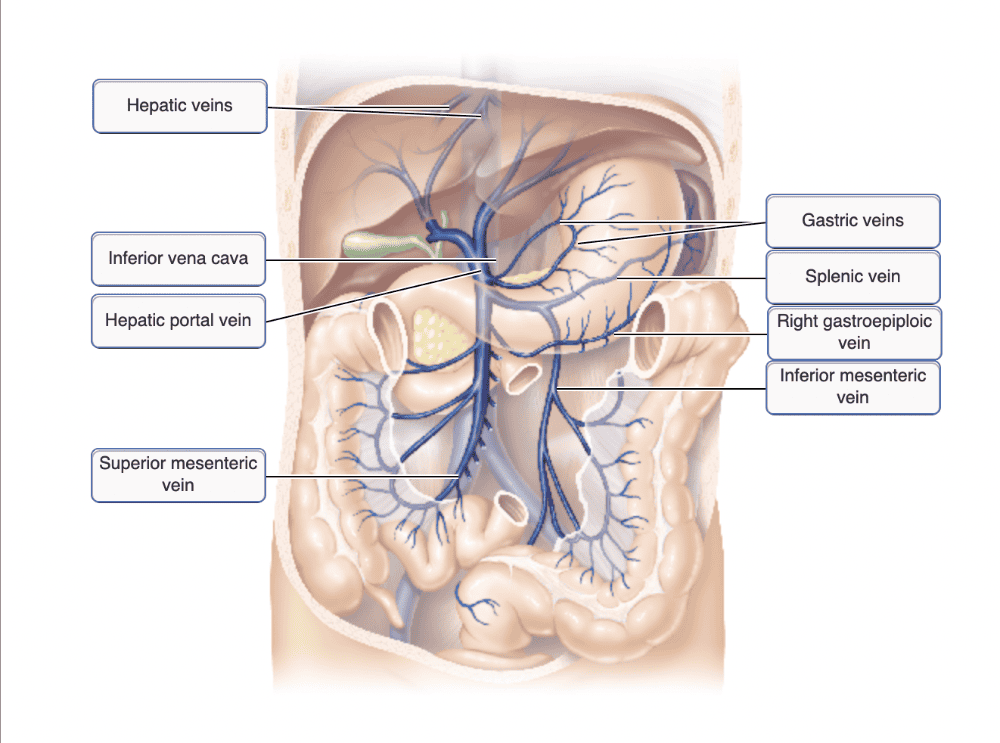

Drag the appropriate labels to their respective targets.

Drag the appropriate labels to their respective targets.